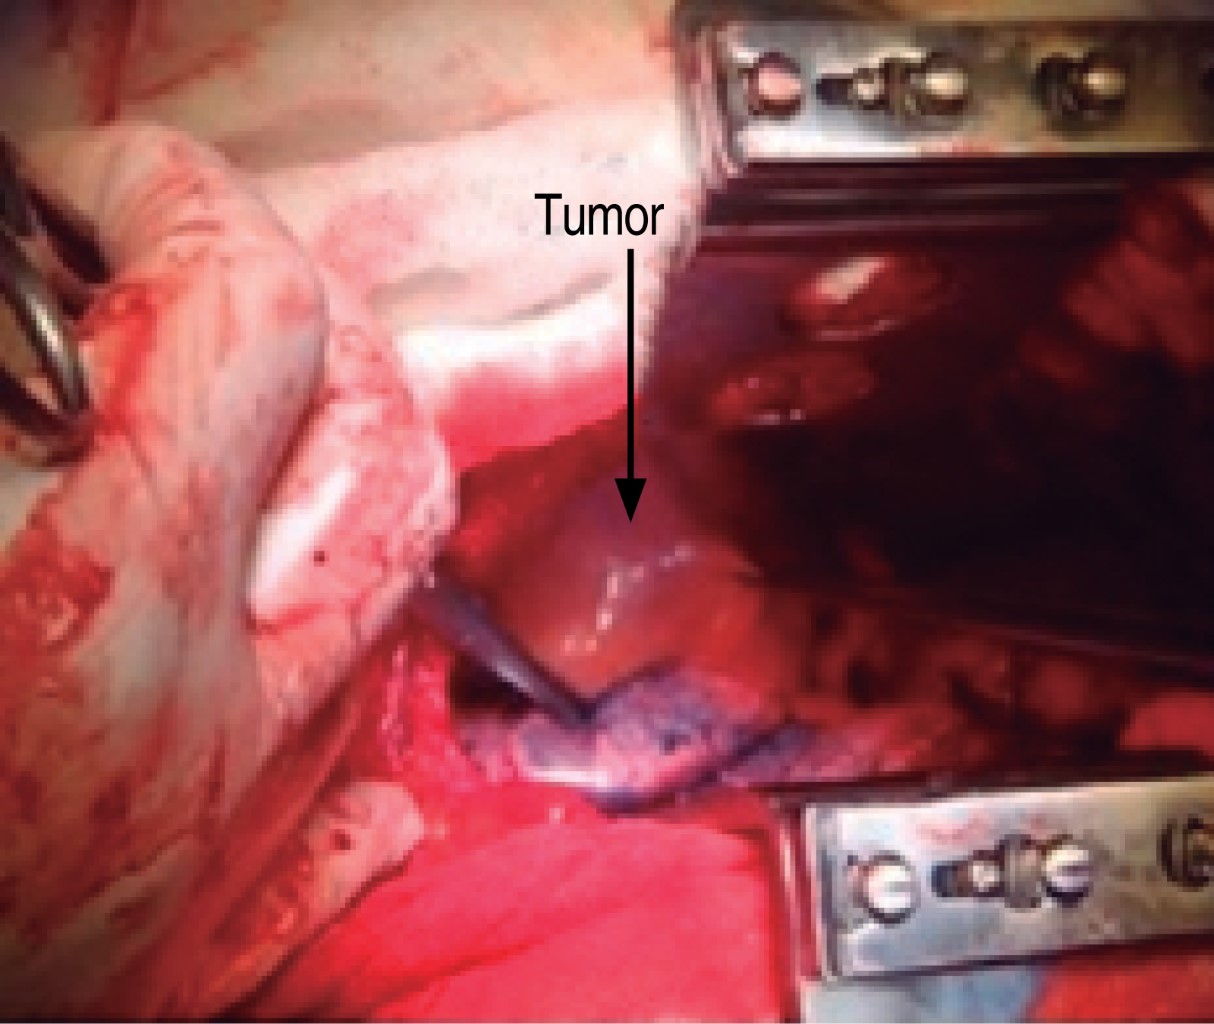

This is a 47-year-old man who had been managed for 15 years for gout, so he went to rheumatology consultation, where he refers respiratory symptoms of three months of evolution characterized by dry cough in accesses, in addition to facial edema and upper extremities. In his last consultation he requested a routine chest X-ray where a mediastinal widening was observed, so a computed tomography scan was performed, which showed a mass in the middle mediastinum of approximately 7 × 5 centimeters in diameter, with extrinsic compression of the superior vena cava and azygos vein, elevation of the homolateral hemidiaphragm, in addition to severe hepatomegaly (Figure 1).

A right posterolateral thoracotomy was performed because we did not have equipment to perform minimally invasive surgery, finding a tumor in the middle mediastinum of approximately 7 × 5 × 4 cm, with a hard consistency, encapsulated, and attached to the lateral wall to the superior vena cava, upper edge of the azygos vein and intrathoracic trachea, and to its lower portion to the azygos vein (Figure 2). The tumor was completely excised (Figure 3). In the immediate postoperative period, the patient showed no complications and was extubated. The control thoracic X-ray showed complete pulmonary expansion (Figure 4).

Figure 1

Figure 2